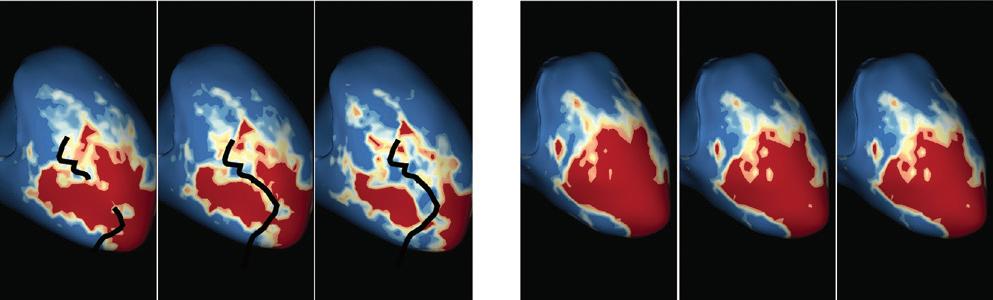

Figure 2: Gaps in Ablation Lesions After Pulmonary Vein Isolation

Preprocedural LGE-MRI (1 day before PVI) A B Post-ablation LGE-MRI (3 months after PVI) Preprocedural LGE-MRI (1 day before PVI) Post-ablation LGE-MRI (3 months after PVI) LIPV LAA RIPV LSPV RSPV LIPV LAA Superior view Superior view Superior view Superior view RIPV LSPV RSPV LIPV LAA RIPV LSPV RSPV LIPV LAA RIPV LSPV RSPV

Figure 3: Agreement Between Electroanatomical Mapping and 3 Months Late Gadolinium Enhancement-MRI Regarding Gap Localisation

LGE-MRI-guided Repeat Ablation

Accumulating evidence indicates that LGE-MRI can detect and localise the gaps in ablation lesions with high accuracy (Figure 3).5–7 14 Overall, the accuracy and in particular the high sensitivity in the detection of gaps appears to be sufficient for LGE-MRI-guided repeat ablation – not only in the context of AF (Figure 4), but also with respect to post-ablation reentrant atrial arrhythmias (Figure 5).5 7 14

LPV entry

RPV entry

Activation maps of the LPVs and RPVs with conduction vectors (CARTO 3, coherent mapping with Pentaray catheter, Biosense Webster) indicating the entry site of the activation wave front (functional gaps) as detected during a repeat ablation procedure. Corresponding gaps detected by prior late gadolinium enhancement (LGE)-MRI (3 months post index ablation) are displayed in the small boxes. Colour-coding of the LGE maps (ADAS 3D software) is based on image intensity ratios with thresholds for dense scar (>1.32 red) and border zone (1.2–1.32 yellow), respectively. White arrows indicate localised functional gaps and LGE discontinuities, respectively. LPV = left pulmonary vein; RPV = right pulmonary vein.